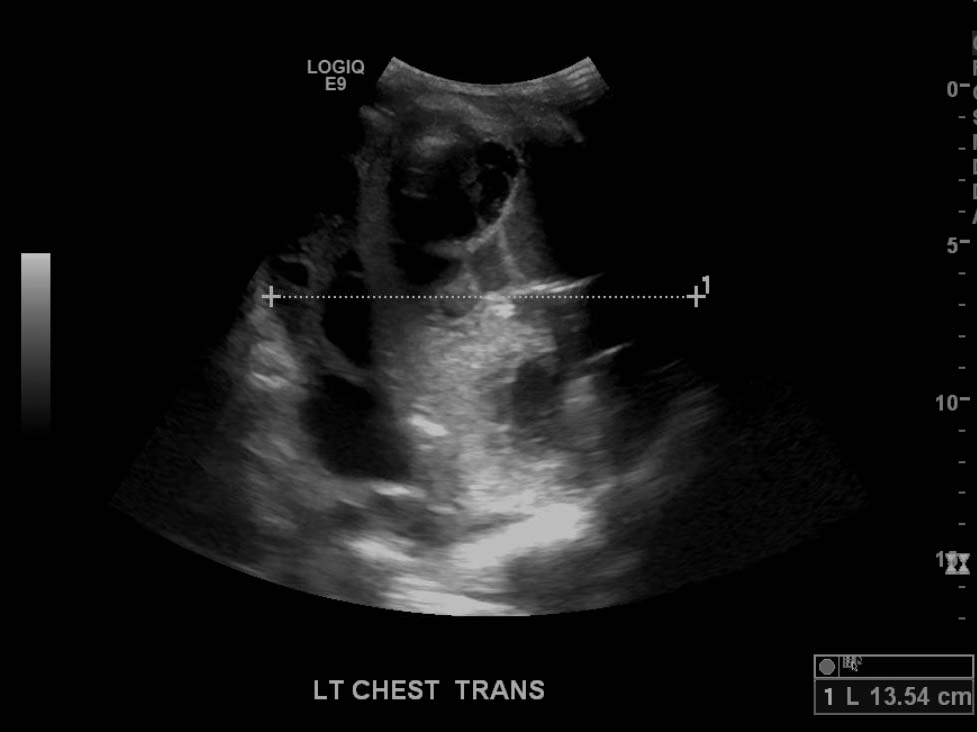

- Large, complex, multiseptated left pleural fluid collection

- Adjacent airspace consolidation in the left lung with air bronchograms

Large, complex, multiseptated left pleural fluid collection with adjacent airspace consolidation, concerning for pneumonia and empyema. No discernible right pleural effusion.

- Ultrasound can be very useful in evaluating pleural fluid collections as it is more sensitive for detecting pleural fluid than radiography and can be used for procedural planning and guidance

- Worry about a complicated effusion (which may represent empyema, hemothorax, or malignant effusion depending on the clinical scenario) if the fluid collection has hyperechoic areas or if it contains internal septations